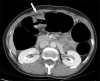

Purpose: We sought to evaluate the clinical usefulness of CT colonography (CTC) after incomplete conventional colonoscopy (CC) for occlusive colorectal cancer (CRC) according to the tumor location.

Materials and methods: Seventy-five patients with occlusive CRC underwent subsequent CTC immediately after incomplete CC. Fifty-nine patients had distal CRC and 16 had proximal colon cancer. Experienced radiologists prospectively analyzed the location, length, and TNM staging of the main tumor. The colorectal polyps in the remaining colorectum and additional extraluminal findings were also recorded. Sixty-seven patients underwent colorectal resection. We retrospectively analyzed the surgical outcome and correlated CTC and CC findings.

Results: The overall accuracies of tumor staging were: T staging, 86%; N staging (nodal positivity), 70% (80%); and intra-abdominal M staging, 94%. Additional colonic polyps were found in 23 patients. Six synchronous carcinomas were detected (9%); three in the proximal colon and three in the distal colon of occlusion. Clinically significant localization errors at CC were noted in 8 patients (12%, 5 proximal colon cancers and 3 distal CRCs) and were corrected by CTC. After CTC, the surgeons modified the initial surgical plan in 11 cases (16%).

Conclusion: In occlusive CRC, CTC is not only useful in the evaluation of the proximal bowel, but can also provide surgeons with accurate information about staging and tumor localization. CTC is recommended when endoscopists encounter occlusive CRC, regardless of tumor location.